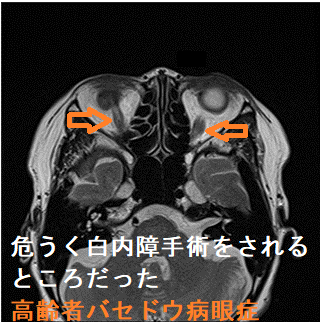

危うく眼科で白内障手術をされるところだった活動性甲状腺眼症・バセドウ病眼症(74歳女性)1

危うく眼科で白内障手術をされるところだった活動性甲状腺眼症・バセドウ病眼症(74歳女性) MRI T2強調画像;両側の外直筋、下直筋に炎症を認める。